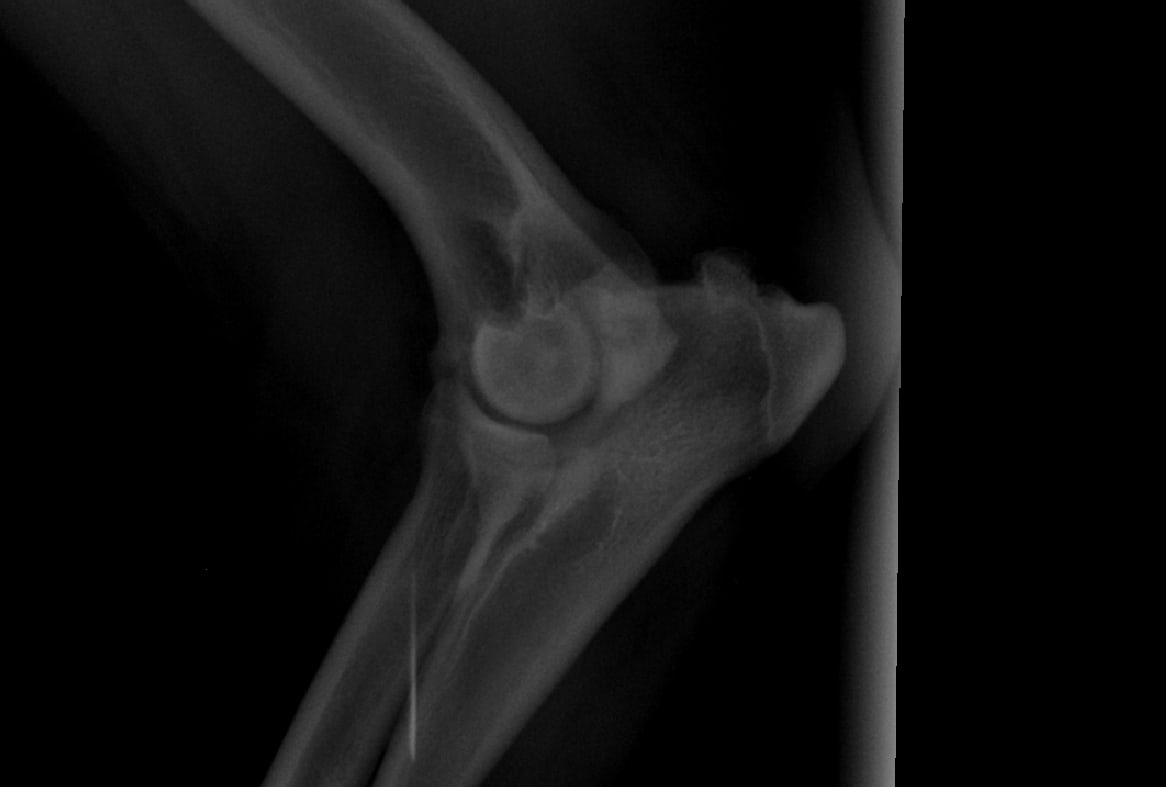

Pet's info: Dog | Rottweiler | Male | neutered | 4 years and 5 months old | 110 lbs

Hi, I recently asked a question on here regarding my dog. we took him for a 2nd opinion regarding his right front leg. they too cannot see what is wrong - the vet suspects bone cancer or broken cartridge in his humorous. All they did was give us anti inflams for 4 weeks and said come back for more xtrays. My question. if it is bone cancer - then Why are they making us wait for it to progress. I have attached the Xrays again. Why have they not done a bone biopsy? this is our 2nd opinion already

I don't see any abnormalities in the radiographs that you show. Bone cancer can occasionally be difficult to diagnose before it is very severe. To biopsy a bone for possible cancer, you need to know where in the bone to sample, so it is not as simple as just picking any part you want. Advanced diagnostics like MRI or CT may be more helpful at looking more closely at the soft tissue (muscles, tendons, ligaments) and bone to see if there are any abnormalities. You will likely need a referral to a specialty hospital for this procedure. If you are concerned about something life-threatening like bone cancer, I would recommend that you speak with either vet about a referral.